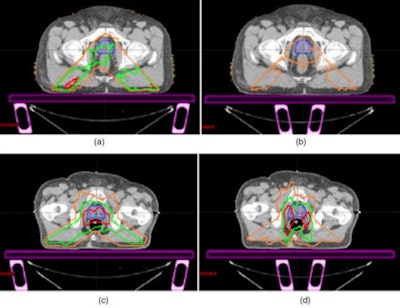

| Representative IMRT and RapidArc dose differences between the no-couch scenario and other plan iterations: (a) IMRT rails-out, (b) IMRT rails-in, (c) RapidArc rails-out, and (d) RapidArc rails-in, showing spatially the areas of dose loss due to the couch and rails. Differences of 1 Gy (orange), 2 Gy (green), and 3 Gy (red) are shown. The prostate/CTV is shown in solid colorwash. |

The researchers then used dose-volume histograms to evaluate changes in target dose and coverage. For IMRT, the average radiation dose loss from a prescribed 76 Gy was 4.2% (3.2 Gy) for the rails-out plan, with a maximum loss of 5.1% seen in one patient. With the rails in, approximately 2% (1.5 Gy) was lost. For RapidArc plans, dose losses were 3.2% (2.4 Gy) and 2.9% (2.2 Gy) for the rails-out and rails-in plans, respectively, with a maximum loss of 4%.

Kry and colleagues then examined the percentage of the target covered by the prescribed dose. When the couch and rails were included, target coverage dropped to 35% (rails-out) and 84% (rails-in). For RapidArc plans, coverage of the prostate dropped from 99% (no-couch) to 18% (rails-out) and 17% (rails-in).